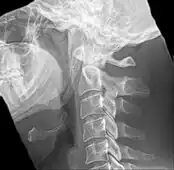

![]() Vistas lateral y anteroposterior de una radiografía cervical que muestra osificación del ligamento estilohioideo. | ||

La apófisis alargada o calcificación del ligamento estilohioideo suelen mostrarse fácilmente a través de una prueba radiográfica. De forma adicional se puede realizar un TAC para confirmar el diagnóstico y ver qué estructuras están siendo afectadas.[10]